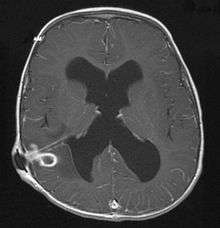

_--_showing_a_small_ring-enhancing_lesion_with_mild_surrounding_edema_adjacent_to_the_ventricular_catheter_and_ventricular_dilatation..jpg)

The diagnosis is established by a computed tomography (CT) (with contrast) examination. At the initial phase of the inflammation (which is referred to as cerebritis), the immature lesion does not have a capsule and it may be difficult to distinguish it from other space-occupying lesions or infarcts of the brain. Within 4–5 days the inflammation and the concomitant dead brain tissue are surrounded with a capsule, which gives the lesion the famous ring-enhancing lesion appearance on CT examination with contrast (since intravenously applied contrast material can not pass through the capsule, it is collected around the lesion and looks as a ring surrounding the relatively dark lesion). Lumbar puncture procedure, which is performed in many infectious disorders of the central nervous system is contraindicated in this condition (as it is in all space-occupying lesions of the brain) because removing a certain portion of the cerebrospinal fluid may alter the concrete intracranial pressure balances and causes the brain tissue to move across structures within the skull (brain herniation).

Ring enhancement may also be observed in cerebral hemorrhages (bleeding) and some brain tumors. However, in the presence of the rapidly progressive course with fever, focal neurologic findings (hemiparesis, aphasia etc.) and signs of increased intracranial pressure, the most likely diagnosis should be the brain abscess.